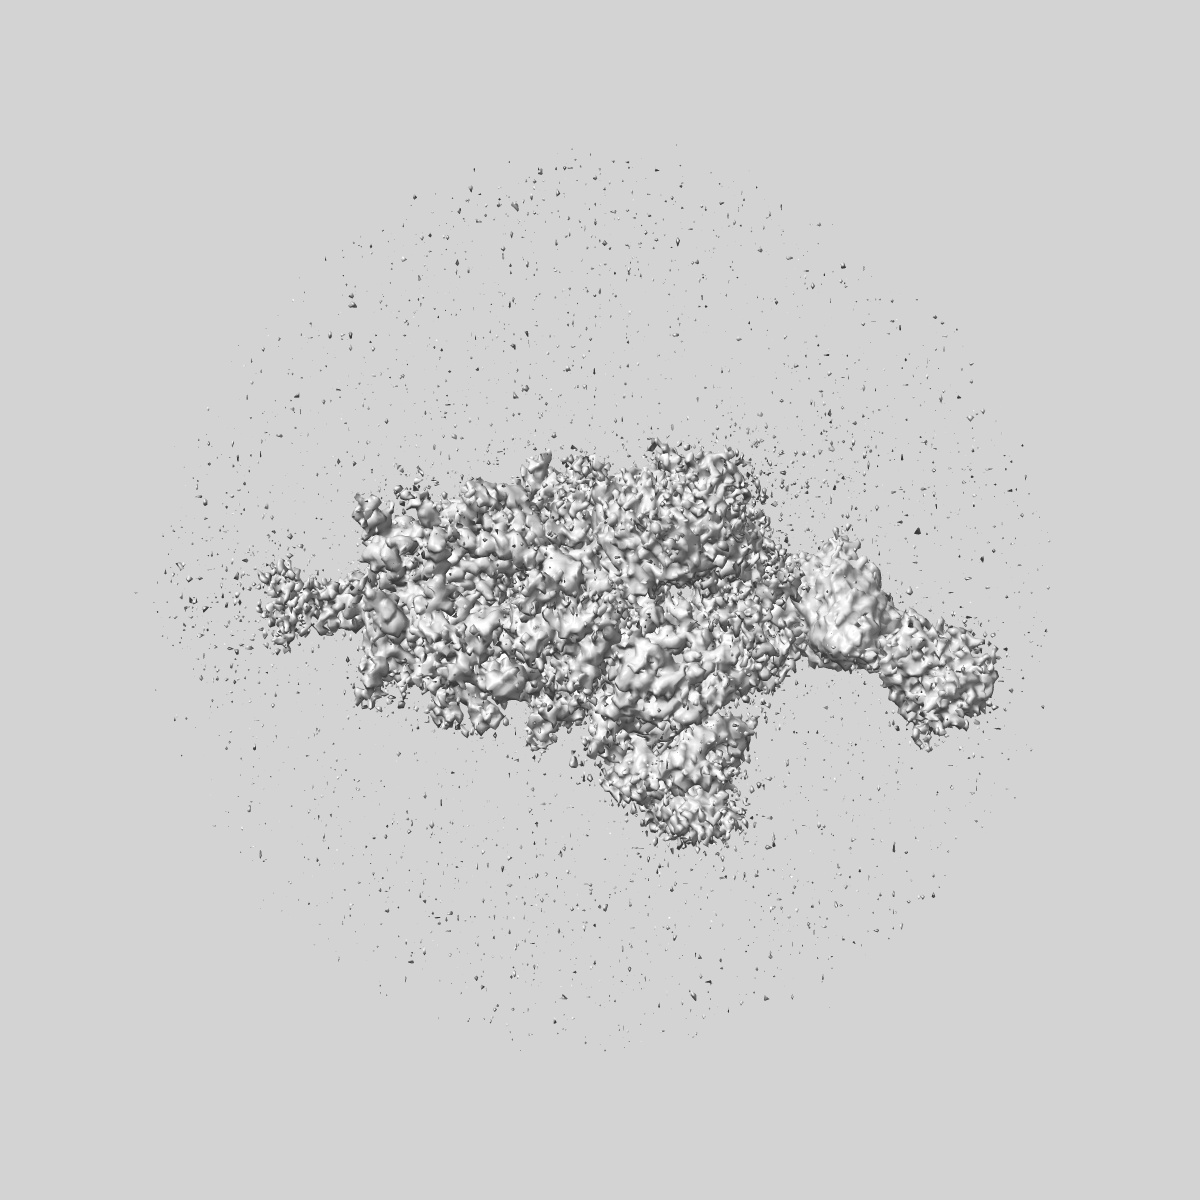

SARS-CoV-2 Wuhan Spike ectodomain in complex with human polyclonal antibody ModWu-RBD2 (mRNA-1273 vaccine)

Sample: SARS-CoV-2 Wuhan spike ectodomain in complex with human polyclonal antibody ModWu-RBD2

Single-particle3.2 Å